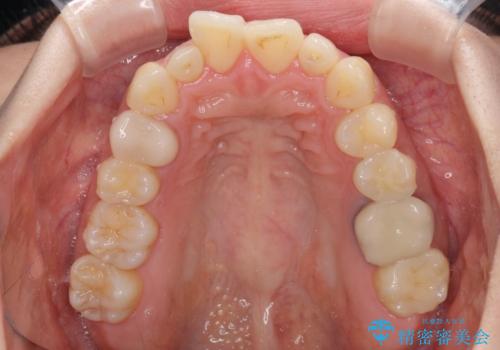

- 上顎前歯の突出感を気にして来院された患者様です。

下顎前歯2本が先天欠損しており、上顎歯列に対して、下顎歯列がアンバランスに小さい状況でした。

左右上顎側切歯2本が矮小歯であるため、上顎の抜歯ではなく、IPR(歯と歯の間を削る)と歯列全体の後方移動によってバランスを整えることとしました。

歯列のバランスが悪く、インビザライン矯正特有の奥歯の噛みにくさがなかなか改善されず、治療期間が長期化してしまいました。